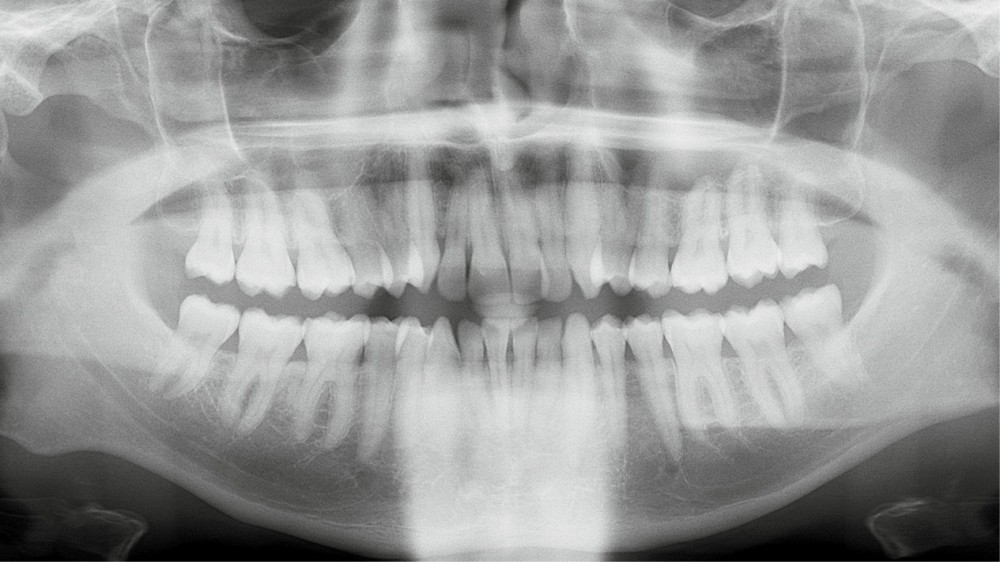

Diagnostic (fig. 1a-i)

Le patient consulte initialement pour des défauts d’alignement. L’examen clinique confirme l’existence d’un encombrement antérieur bimaxillaire, mais révèle aussi la présence d’une Classe II dentaire sévère, d’une exoclusion de la 27 et de troubles parodontaux (peu ou absence de papilles inter-dentaires). Sur le plan squelettique, le patient est relativement équilibré avec un profil harmonieux.